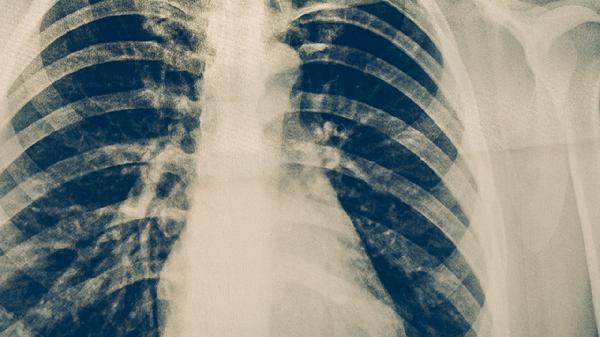

肺癌患者除规范治疗外,需保持均衡饮食,适当补充优质蛋白和维生素。根据体能状况进行适度活动,如散步、太极拳等。定期复查影像学检查和肿瘤标志物,监测病情变化。保持良好心态,避免过度劳累,戒烟并远离二手烟环境。出现咳嗽加重、咯血、胸痛等症状时应及时就诊。